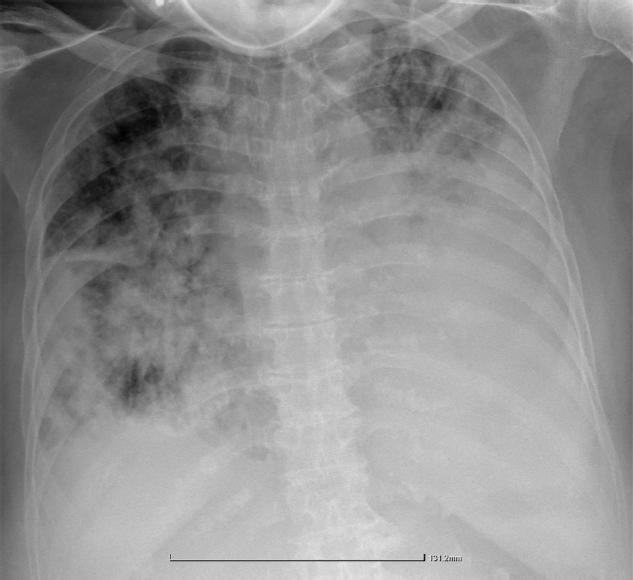

Thoracic CT scan at final presentation. Marked progression and confluence of bilateral consolidations with increased pleural effusion.

The third emergency admission occurred shortly after. The patient demonstrated significant clinical and imaging progression (CT scan), with acute respiratory failure, enlargement and confluence of bilateral consolidations, and reaccumulation of pleural effusion (Figure 4). This time, the prognosis was poor and her condition worsened. She developed a significant infectious-inflammatory syndrome progressing to sepsis, originating from the lungs. Cytologic examination of the pleural fluid then raised suspicion for a secondary neoplastic aetiology. CT-guided transthoracic pulmonary biopsy was performed, and histopathology revealed invasive mucinous adenocarcinoma with a limited micropapillary pattern, raising suspicion for ‘pneumonic-type’ adenocarcinoma when correlated with the clinical and imaging presentation. Due to unfavourable disease progression, the patient was transferred to the intensive care unit (ICU), where she subsequently died (Figure 5).